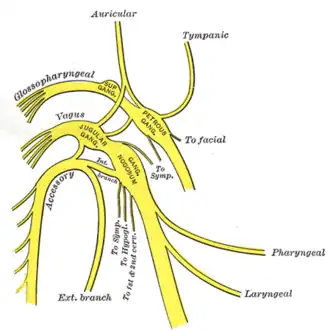

Plan of the upper portions of the glossopharyngeal, vagus, and accessory nerves. | |

Branches

- Pharyngeal nerve

- Superior laryngeal nerve

- Aortic nerve

- Superior cervical cardiac branches of vagus nerve

- Inferior cervical cardiac branch

- Recurrent laryngeal nerve

- Thoracic cardiac branches

- Branches to the pulmonary plexus

- Branches to the esophageal plexus

- Anterior vagal trunk

- Posterior vagal trunk